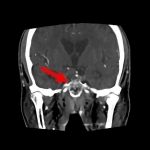

断層撮影